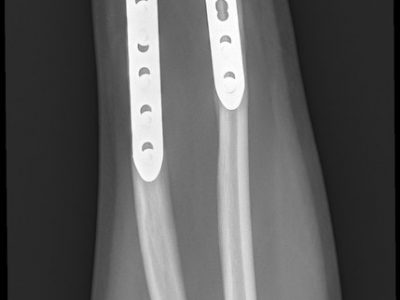

Παρακάτω παρατίθενται ακτινογραφίες καταγμάτων του άνω άκρου που αντιμετωπίζονται με εσωτερική οστεοσύνθεση ή επανορθωτική χειρουργική με αρθροπλαστική.